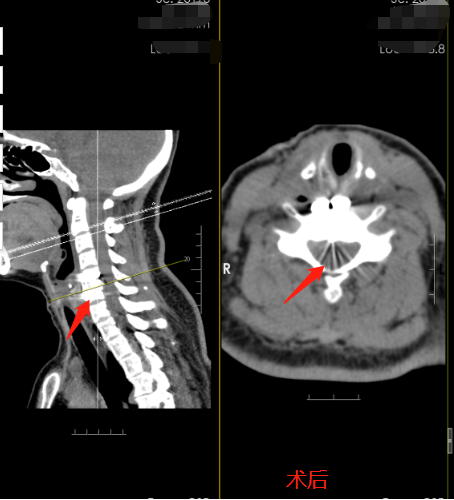

4月28日彭阿姨便马不停蹄踏上了南下广州的路。29日顺利入住的广东三九脑科医院神经外十科。主管医生热情的接待了她,详细询问病史后完善了相关的检查。医生解释,彭阿姨的颈椎病是属于神经根型颈椎病,是颈椎退变引起神经根的病变,主要表现为颈肩部疼痛、手臂和手指的麻木和无力,大部分经过颈椎牵引、针灸等物理治疗即可,像彭阿姨的这种经过保守治疗不能缓解的,可行手术治疗。手术需沿着颈部自然的纹理做3cm的切口,术后疤痕能最小化,显微镜下精细化的操作做到神经根充分减压,全程的神经电生理监测预警系统可以为手术保驾护航,出现瘫痪的概率极低。很快,神经外十科团队为彭阿姨制定了缜密的手术方案。4月30日,医生为彭阿姨进行了颈前路C5-6椎间盘切除减压融合术+神经根减压术。术后第一天彭阿姨惊喜的发现右手麻木消失,右手也可以抬起来了。彭阿姨的丈夫高兴的说,终于可以看见阿姨有笑容了。术后第五天,满心欢喜的出院回到湖南老家。